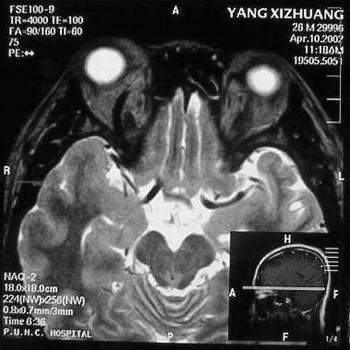

MRI及增强结果如下:

患者压颈及其它Valsava试验结果阴性。从MRI分析,在T1、T2、T+C检查该支血管均为明显流空现象,说明该血管血流速度很快,而从走行和分布看,眼上静脉可能性很大。也许也不能除外异常的眼动脉或异常血管。眶内主要可能的血管病变包括颈内动脉海绵窦瘘(高流窦)、AVM、眼眶静脉曲张、海绵状血管瘤、静脉性血管瘤、毛细血管瘤和眶内动脉瘤。。 1、颈内动脉海绵窦瘘:该患者临床有一部分支持该诊断。但从影像分析,海绵窦未见明显扩张;眼外肌未见明显充血扩张的长T1、长T2信号;颈内动脉海绵窦瘘常可见继发到血栓,可见到短T1、长T2的血栓信号。 2、眼眶静脉曲张:该疾患一般常见于小儿。该患大多数会出现Valsava试验阳性,间歇性突眼。不符合该患。影像学检查,于曲张静脉内常可见血栓和静脉石。所以不符合该患。 3、AVM:患者目前的影像学资料尚不全面,但可符合该诊断。临床上改病常见于30岁左右年轻人,单侧发病,于本患较符合。问题在于临床没有明确的血管杂音,似乎难以解释。 4、该患影像学与海绵状血管瘤差别很大,所以可基本排除此诊断。 5、静脉性血管瘤和毛细血管瘤:MRI中等T1、长T2信号,较易与本病鉴别。 6、眶内动脉瘤:我觉得患者并不能排除本病,但同样,由于波动性阴性,似乎也难以解释。 纵上所述:本人觉得,患者AVM可能性较大,同时不能除外眶内动脉瘤。 关于进一步检查,我觉得DSA价格过于昂贵。是否可先进行彩色多普勒检查,首先可以明确是静脉系统还是动静脉瘘抑或是动脉瘤。第二步,可进行MRA检查,可以清楚地显示海绵窦地相关关系,并可借此诊断或排除颈内动脉海绵窦瘘。如还需第三部检查,可进行MRV检查,对静脉系统进一步评价。三种检查总共的费用2000多圆,但给予我们的信息量已经很丰富了。 敬请各位医师提出自己的见解。 谢谢!

根据MRI显示眼上静脉扩张可能性很大。眼上静脉扩张有几种原因:1.颈内动脉海绵窦瘘,2.眶尖肿瘤,3.甲亢,4.炎性假瘤.病人球结膜充血示静脉回流障碍,动脉瘤可能性小.根据病史,我认为排除1,2.则考虑3,4.查T3,T4.激素作诊断性治疗.